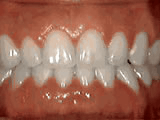

Crowding of the teeth

Patient started treatment at age 11 and wore braces for 26 months. He loves his new smile.